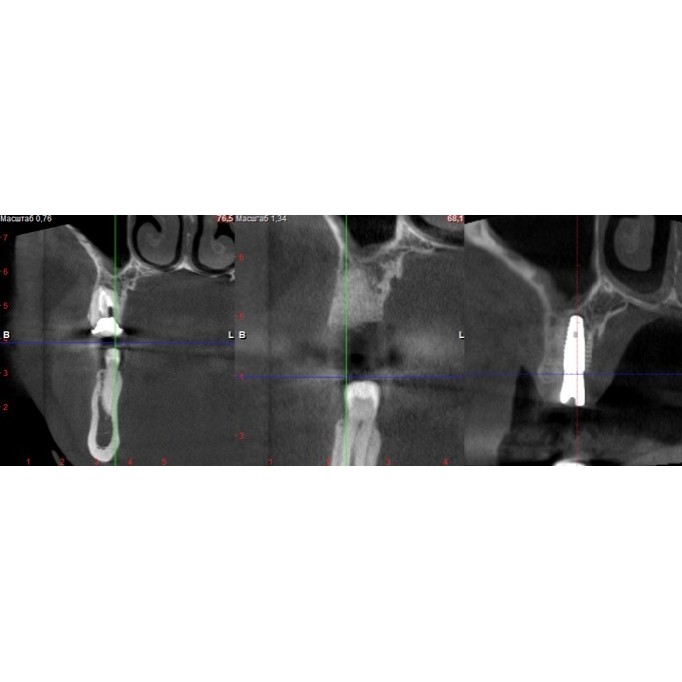

Вступ до імплантації зубівОпис:Імплантація зубів — це сучасний метод відновлення втрачених зуб..

Що таке зубний імплантат?Опис:Зубний імплантат — це штучний корінь, зазвичай виготовлений з титану, ..

Процедура встановлення зубного імплантатуОпис:Встановлення зубного імплантату — це складна, але чіт..